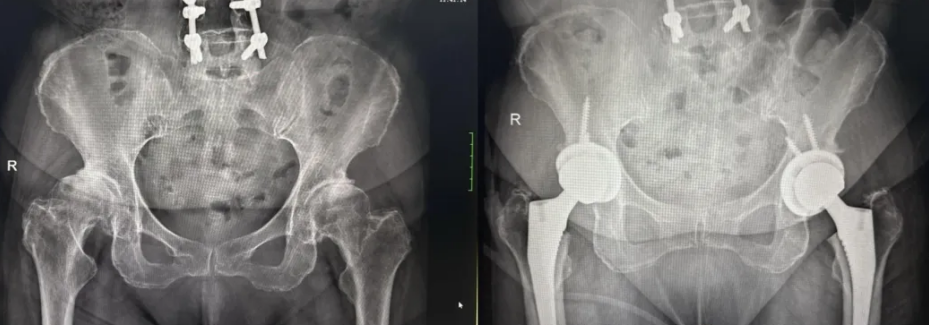

李奶奶则是因髋关节发育不良导致重度骨关节炎,双侧髋关节疼痛多年,保守治疗后症状仍加重。她先是做了右侧手术,此次完成左侧手术。

(▲李奶奶术前术后影像)